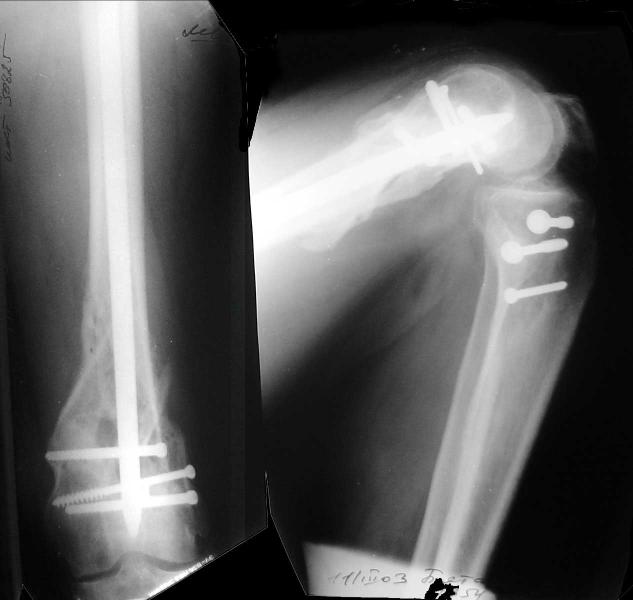

And why LISS is superior here than nail?

Look what we would have done.

I would not say that the LISS is superior to the nail. If I would, I had not post original mail. I wanted to generate discussion. Your option is a very viable one. I feel a little bit shaky the distal femur, but it is just gut feeling no science behind it. Any way nice fixation, congarts!